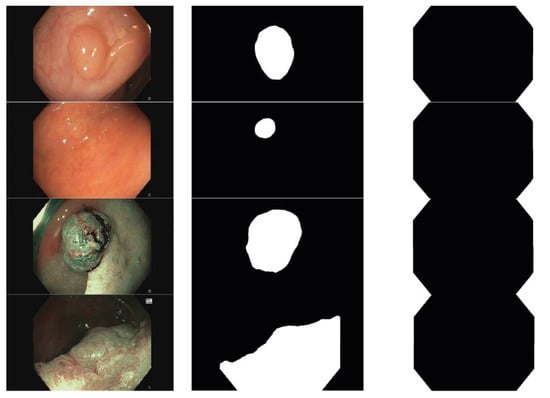

- Frame itself: png files showing the WL or NBI image.

- Mask: Binary mask indicating the area corresponding to the lesion.

- Void: Binary mask indicating the black area of the image.